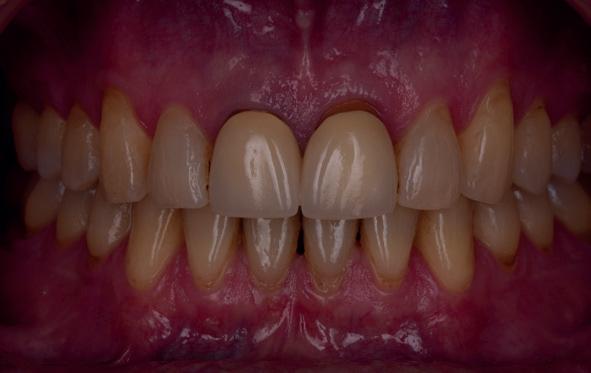

Esthetiek in de tandheelkunde, met name in het front, is een samenspel tussen de roze zachte weefsels en de witte harde weefsels. In het Engels wordt dit ook wel aangeduid met “pink and white esthetics”, waarbij het verkrijgen van correcte pink esthetics over het algemeen een grotere uitdaging vormt dan de white esthetics. Deze roze esthetiek is vooral van belang bij gebitselementen waarbij sprake is van recessie (het terugtrekken van de gingivalijn, waardoor de radix en een langere tand zichtbaar worden). De situatie wordt nog uitdagender wanneer een tand of kies niet is aangelegd, of in het verleden is verwijderd. Het element zorgt er immers voor dat de gingiva rondom de natuurlijke kroon ligt en dat er voldoende weefseldikte rondom deze kroon aanwezig is. Als het element ontbreekt, groeit het alveolaire bot dicht, omdat er geen radix meer is, en daarmee ook de mucosa (wanneer er geen element meer aanwezig is, spreken we niet meer van gingiva maar van mucosa), die dan afgevlakt is. De papillen tussen de afwezige elementen vlakken dan ook af.

Om één of meer afwezige elementen te herstellen bij een vaste voorziening, kan er een etsbrug of kunnen er implantaten worden geplaatst. De esthetiek valt of staat hierbij met de aanvulling van de zachte weefsels, zowel in de vorm van verbreding hiervan als het creëren van een zogenoemd emergence profile –dat wil zeggen dat de tand op een natuurlijk ogende wijze vanuit het tandvlees tevoorschijn moet komen.

Een gezonde, jonge dame had op 8-jarige leeftijd een trauma op school waarbij ze op haar voortanden was gevallen. Volgens haar moeder waren deze voortanden tot onder het tandvlees afgebroken. Nadat ze

via de spoeddienst bij de kaakchirurg terechtkwam, werd daar besloten tot extractie van de 11 en 21. In de opinie van de auteur is dit een te voorbarige behandeling geweest; de kans dat beide centrale incisieven bij een meisje van 8 jaar na een val zodanig beschadigd zijn dat de radices zonder kans op behoud verwijderd moesten worden, is bijzonder klein. Helaas was het kwaad al geschied.

Op 16-jarige leeftijd werd de patiënt door haar behandelend orthodontist naar de auteur verwezen voor een restauratieve oplossing voor de afwezige 11 en 21. In de tussenliggende periode had patiënt een retainer gedragen met twee kunststof tanden (afbeelding 1). Zowel de patiënt als haar moeder hadden een sterke voorkeur voor een implantaat gedragen vaste oplossing. Gezien haar jonge leeftijd was dit echter nog geen optie, omdat er nog verticale groei te verwachten viel. Implanteren op jonge leeftijd – dat wil zeggen vóór het 21e levensjaar – kan resulteren in een infrapositie van het implantaat, omdat de rest van het gebit nog verticaal kan doorgroeien.

Middels shared decision making werd het volgende plan overeengekomen: eerst zou er een etsbrug met vleugels op de 12 en 22 worden vervaardigd, om op 21-jarige leeftijd verder te gaan met implantologie.

Bij klinisch en röntgenologisch onderzoek viel echter op dat radix van de 12 en 22 een convergerende (de radices staan dan naar mesiaal en naar elkaar toe) in plaats van divergerende (radices staan dan van elkaar af) stand had. Door deze convergerende stand van de radices was er in mesio-distale zin geen ruimte voor twee implantaten ter plaatse van de 11 en 21. Er werd daarom besloten, in tegenzin

1. Retainer met twee frontelementen

2. OPT radices 12 en 22 convergeren

3. Vaste apparatuur voor torque 12 en 22

4. OPT radices 12 en 22 divergeren na orthodontische behandeling

van de patiënt, om eerst weer vaste apparatuur terug te plaatsen om de radices in een divergerende stand te plaatsen. Gelukkig verliep deze behandeling voorspoedig. (afbeelding 2 -4). Het volgende behandelplan werd gemaakt:

5. Beginsituatie voor behandeling